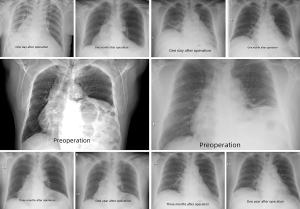

There were no deaths or hospital readmissions. The subjective symptoms of 31 patients (86.11%) improved, especially among those with preoperative digestive symptoms. The diaphragm of the operative side was found to be lower than the contralateral diaphragm on the chest X-ray within 3 months of surgery, and both sides of the diaphragm were basically at the same level after 3 months (Figure 1).

In this study, 86.11% of patients had subjective symptom improvement, especially those with digestive symptoms preoperatively. The operative diaphragm was found to be lower than the contralateral diaphragm on the chest X-ray in the first 3 months after surgery, while both sides of the diaphragm were basically at the same level from the 4th month. No deaths or hospital readmissions were observed. The continuous follow-up of 8 patients showed that lung functions gradually increased over time during the first 6 months, with an average increase of 26.8% and 24.3% in FVC and FEV1, respectively. Previous research has reported 17–30% improvements in FEV1 and FVC in patients who underwent plication (11,21). The potential long-term benefits of diaphragmatic plication are still uncertain. It was reported that patients return to a more or less normal way of life with significant improvement of pulmonary function status (12). In our study, from the 18th month, the lung functions gradually declined to the preoperative level over time and there was no significant difference compared to the preoperative levels, but patients had significant subjective improvements. We suspect that the major purpose of diaphragmatic plication is to balance the position of the heart and abdominal organs, and to thus improve the symptoms of patients to a certain extent.